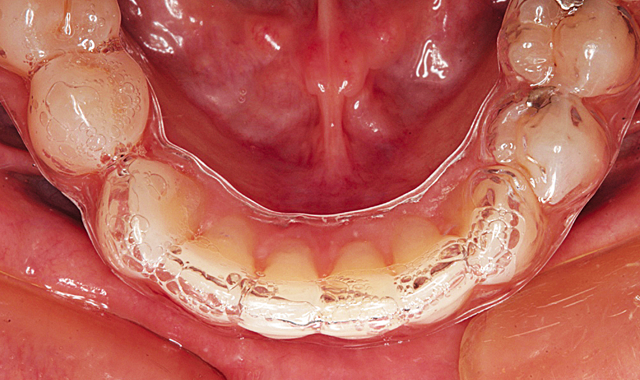

Figure 6 shows the aligners in place from the retracted facial view. The maxillary aligner at placement is shown from the incisal view in Figure 7. In Figure 8, the mandibular aligner is shown in place also from the incisal view.

Fig. 7

Fig. 8

During the next twelve weeks, Mary wore the two Inman Aligners for at least sixteen hours a day. She presented to the office for additional IPR every two weeks. The Inman Aligner can be seen in place from the incisal view on the maxillary arch after twelve weeks in Figure 9.

Fig. 9

The mandibular aligner is shown in place after 12 weeks in Figure 10. Figure 11 demonstrates the maxillary incisal view showing the aligner removed.